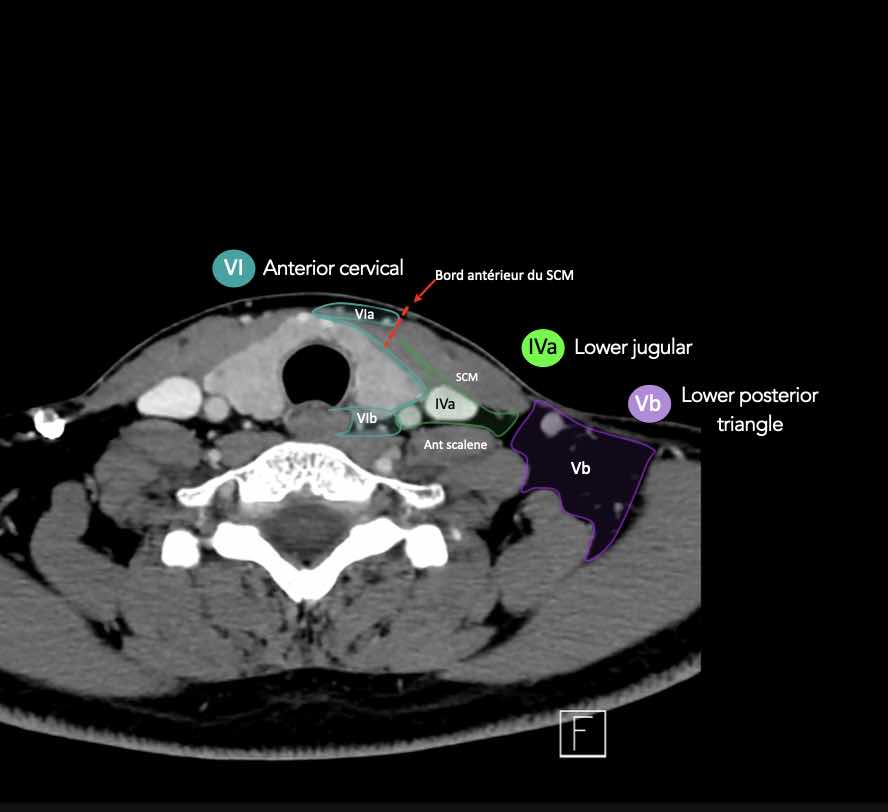

CT Scan Mặt Cắt Ngang (Axial CT)

Các lát cắt CT mặt phẳng ngang tương ứng với hình minh họa tổng quan.

Các lát cắt CT mặt phẳng ngang với hình ảnh chi tiết hơn.

Nhấp vào hình ảnh để phóng to.

IV – Tĩnh mạch cảnh dưới và hố thượng đòn trong

Ranh giới giữa tầng IVa và IVb được xác định tùy ý tại vị trí 2 cm phía trên khớp ức đòn.

Tầng IVa

Các hạch này có nguy cơ chứa di căn từ các ung thư hạ hầu, thanh quản, tuyến giáp và thực quản cổ.

Tầng IVb

Các hạch này có nguy cơ chứa di căn từ các ung thư hạ hầu, thanh quản dưới thanh môn, khí quản, tuyến giáp và thực quản cổ.

VI – Cổ trước

Tầng này chứa các hạch tĩnh mạch cảnh trước nông (tầng VIa) và các hạch sâu hơn bao gồm hạch trước thanh quản, trước khí quản, cạnh khí quản và hạch thần kinh thanh quản quặt ngược (tầng VIb).